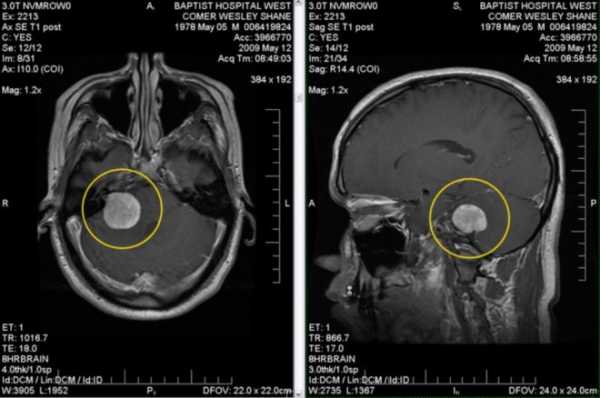

Ключевая роль в неврологической диагностике мозговых опухолей принадлежит рентгенографии, а также компьютерной и магнитно-резонансной томографиям. Эти методики применяют цифровую обработку результата рентгенологического обследования, что выявляет расположение и форму раковой опухоли.

Важнейшим инструментом диагностики опухоли головного мозга является компьютерная томография. Благодаря этому исследованию вы можете определить тип опухоли головного мозга, оценить ее состояние и угрозу инвагинации.

Несмотря на то, что компьютерная томография дает очень много информации о величине и расположении опухоли, что, в сочетании с другими факторами, позволяет определить ее тип, но для точного диагноза выполняется стереотаксическая биопсия с целью получения материала для оценки гистопатологии.

- Магнитно-резонансной томографии с применением контрастного вещества. Эту процедуру назначают, если внешний осмотр показал отклонения. Благодаря исследованию можно выявить начало развития опухолевого процесса и подобрать подходящий курс лечения.